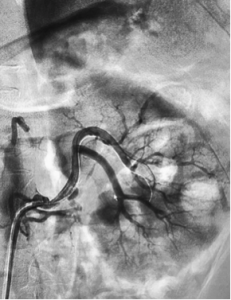

Bệnh nhân (BN) nam 53 tuổi, vào viện vì đau hông lưng trái đột ngột. Tiền sử: THA – rối loạn lipid máu điều trị không đều. Bệnh nhân đau hông lưng trái lan ra trước từng cơn 4 ngày, kèm tiểu buốt, tiểu máu, không sốt. Bệnh nhân nhập viện trong tình trạng da, niêm mạc bình thường, HA: 120/70mmHg, nhiệt độ 36,5 độ C, vỗ hông lưng (-), bụng mềm, các bộ phận khác không có gì đặc biệt. Xét nghiệm máu Ure 6,2 mmol/l, creatinin 155 µmol/l, AST/ALT 70/96 U/l, máu lắng tăng (giờ 1: 75mm, giờ 2: 87mm); nước tiểu có protein niệu, không có hồng cầu, bạch cầu; các xét nghiệm khác, siêu âm bụng, X quang phổi bình thường. BN được chỉ định chụp CT ổ bụng có tiêm cản quang, trên phim chụp CT bụng thấy hình ảnh hai động mạch thận trái, động mạch trước bể tách cao hơn và có hình ảnh bóc tách ở vị trí 1/3 giữa, có lòng giả, thành động mạch sau vị trí bóc tách dày do huyết khối trong thành, nhu mô 1/3 trên kém ngấm thuốc do thiếu máu, có vài ổ hoại tử không ngấm thuốc cản quang kích thước dưới 10mm (hình 1). Động mạch sau bể tách thấp hơn, thành mạch và lòng mạch bình thường, không có hình ảnh thiếu máu cực dưới thận. BN được điều trị nội khoa 3 ngày với Aspirin 81mg/ngày, clopidogrel (Plavix) 75mg/ngày, rosuvastatin (Crestor) 10mg/ngày, paracetamol 1g/ngày. Chụp mạch số hoá xoá nền động mạch thận cho thấy thấy hình ảnh tương tự với cắt lớp vi tính, điểm bóc tách của động mạch trước bể bắt đầu từ cách gốc 10mm, kéo dài khoảng 15 mm gây hẹp lòng thật, lòng giả còn lưu thông thuốc cản quang kích thước khoảng 3x2mm. Tiến hành can thiệp đặt một stent Biomine 4 x 19mm qua đoạn mạch thận tổn thương (hình 2). Sau đặt stent 1 ngày, BN không đau thắt lưng, không rối loạn tiểu tiện, thăm khám các bộ phận không thấy bất thường; xét nghiệm ure: 6,4 mmol/l, creatinin 115 µmol/l, AST/ALT 81/136 U/l, tổng phân tích nước tiểu bình thường. BN ra viện tiếp tục dùng clopidogrel/ aspirin (Duoplavin) 75/100mg/ngày, Crestor 10mg/ngày. Sau 1 tháng, BN tái khám, xét nghiệm ure 5,7mmol/l, creatinin 119 µmol/l, AST/ALT 36/56 U/L, hình ảnh chụp CT ổ bụng có tiêm cản quang thấy động mạch thận trái lưu thông tốt và Stent nở hoàn toàn, không thấy lòng giả, nhu mô thận thuộc vùng cấp máu của động mạch trước bể hồi phục gần hoàn toàn (hình 3).

Hình 2: Đặt stent động mạch thận vị trí bóc tách